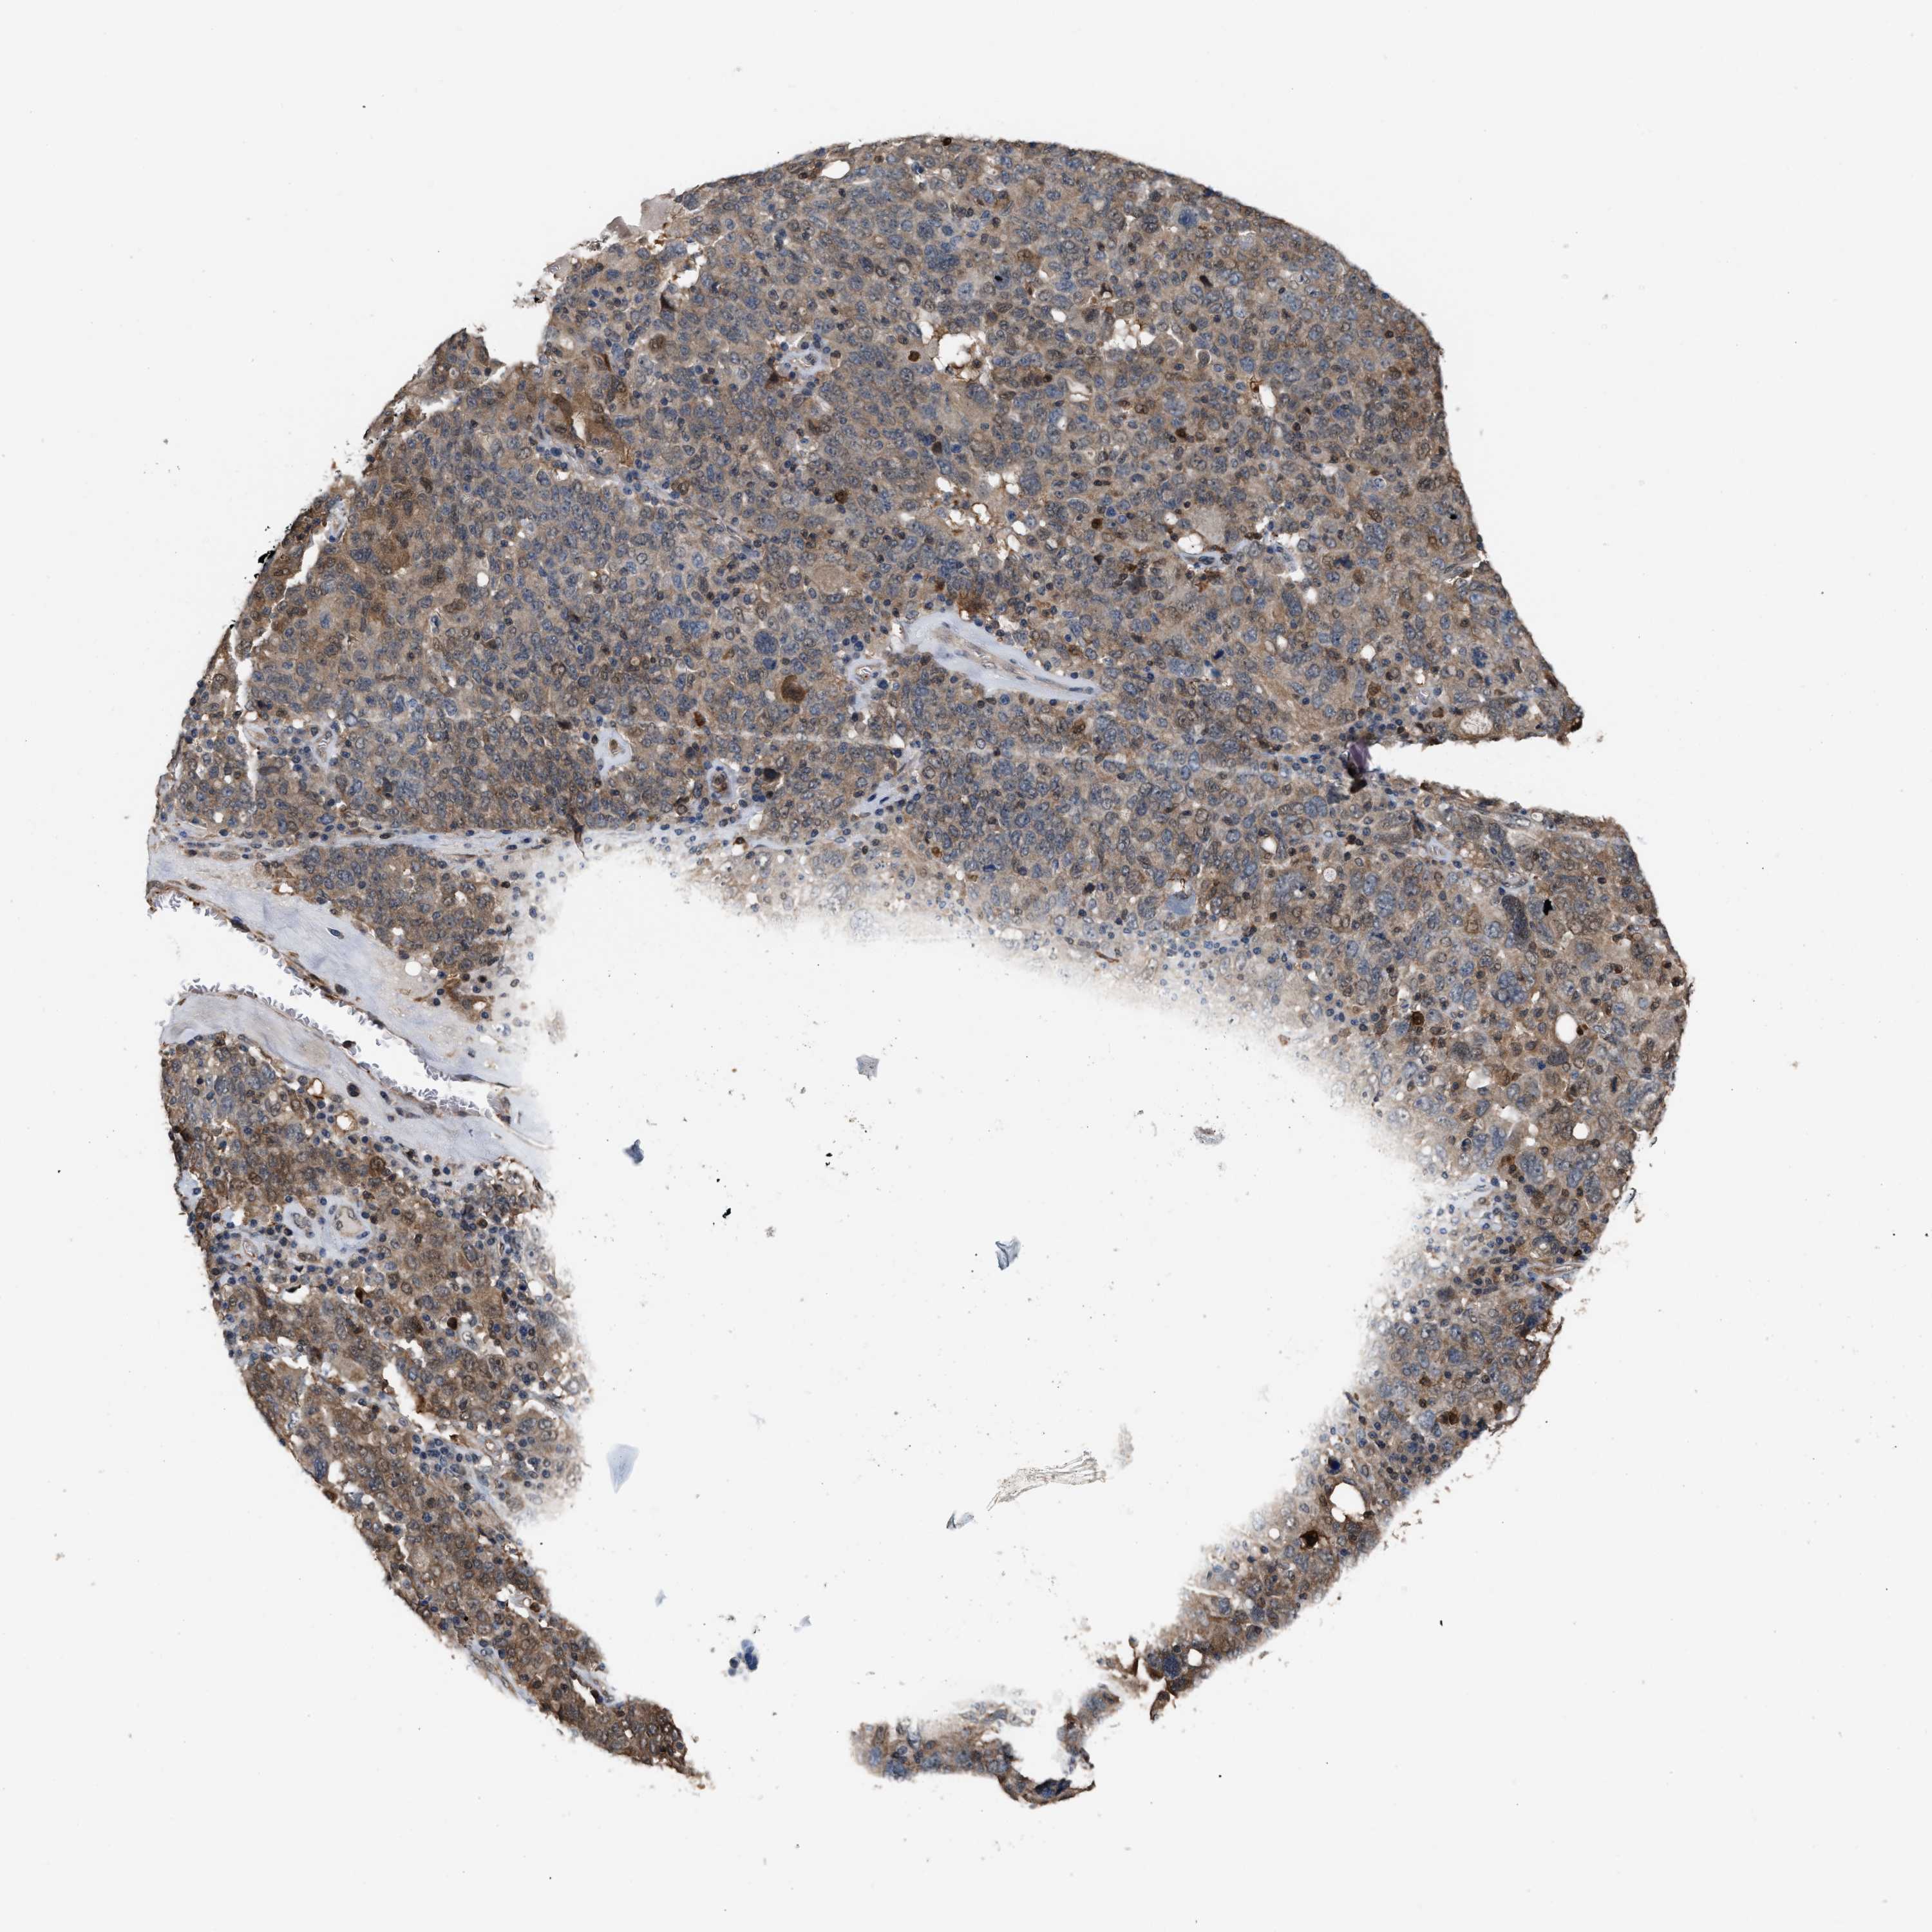

OVARIAN CANCER - Protein expressioni

A mouse-over function shows sample information and annotation data. Click on an image to view it in a full screen mode. Samples can be filtered based on level of antibody staining by selecting one or several of the following categories: high, medium, low and not detected. The assay and annotation is described here.

Note that samples used for immunohistochemistry by the Human Protein Atlas do not correspond to samples in the TCGA dataset.

Antibody stainingi

Antibody staining in the annotated cell types in the current human tissue is reported as not detected, low, medium, or high, based on conventional immunohistochemistry profiling in selected tissues. This score is based on the combination of the staining intensity and fraction of stained cells.

Each image is clickable and will lead to virtual microscopy that enables deeper exploration of all samples and also displays staining intensity scores, fraction scores and subcellular localization as well as patient and tissue information for each sample.

Antibody HPA019735

Staining

High

Medium

Low

Not detected

Intensity

Strong

Moderate

Weak

Negative

Quantity

>75%

75%-25%

<25%

None

Location

Nuclear

Cytoplasmic/membranous

Cytoplasmic/membranous,nuclear

Cystadenocarcinoma, serous, NOS

Carcinoma, endometroid

Cystadenocarcinoma, mucinous, NOS

Carcinoma, NOS